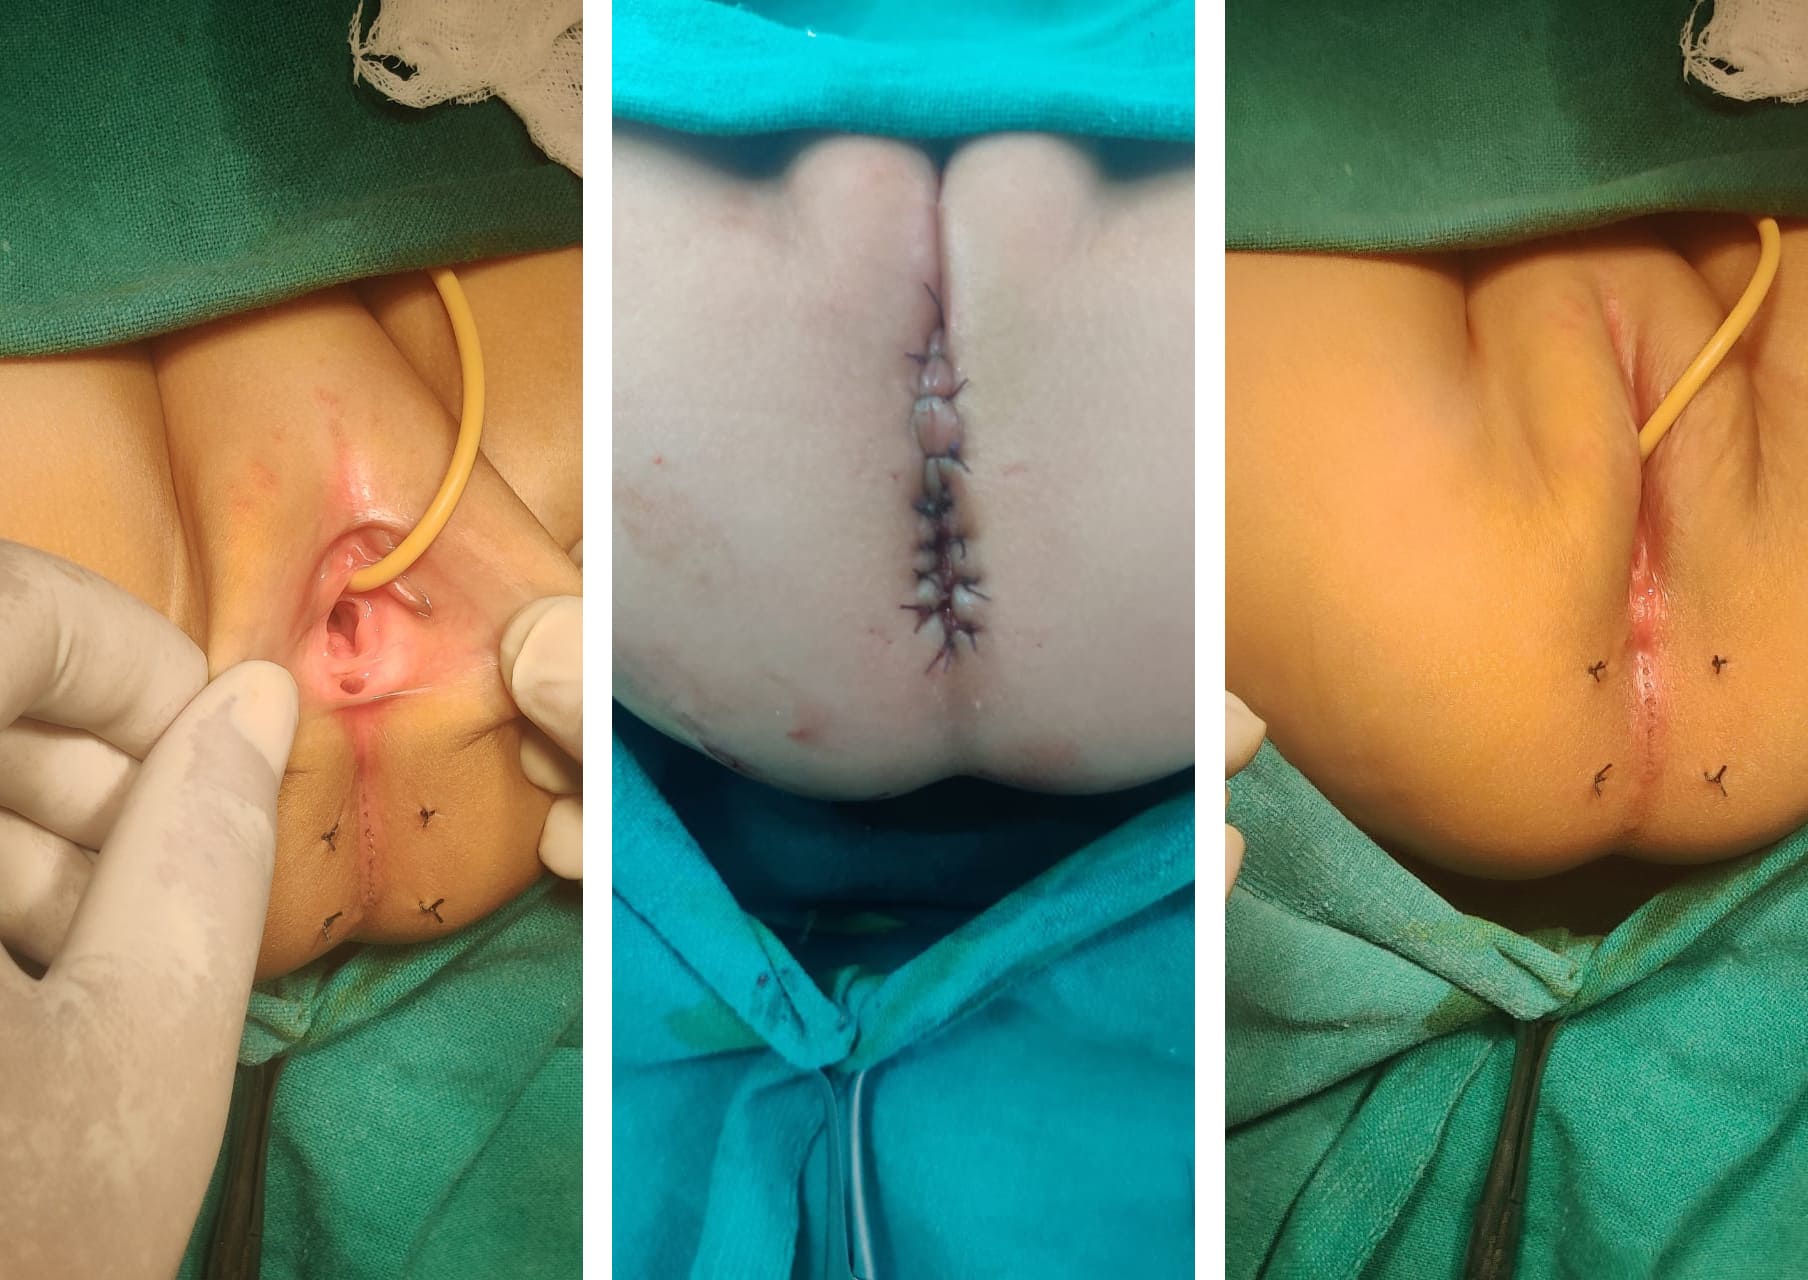

Anorectal malformation with scrotal fistula with bifid scrotum

Creat neoanus with improvement of scrotal appearance as normal